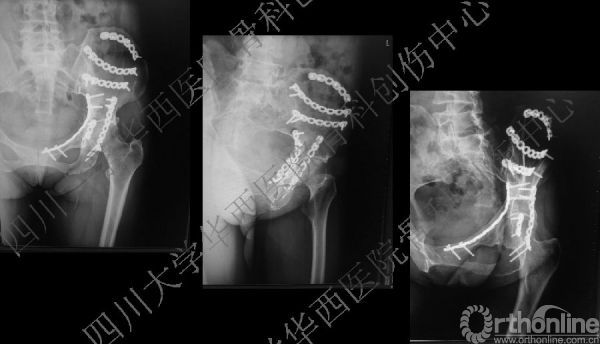

术后CT

术后冠状位及横切面CT扫描,负重区解剖复位

术后CT也证实骨盆形态正常。